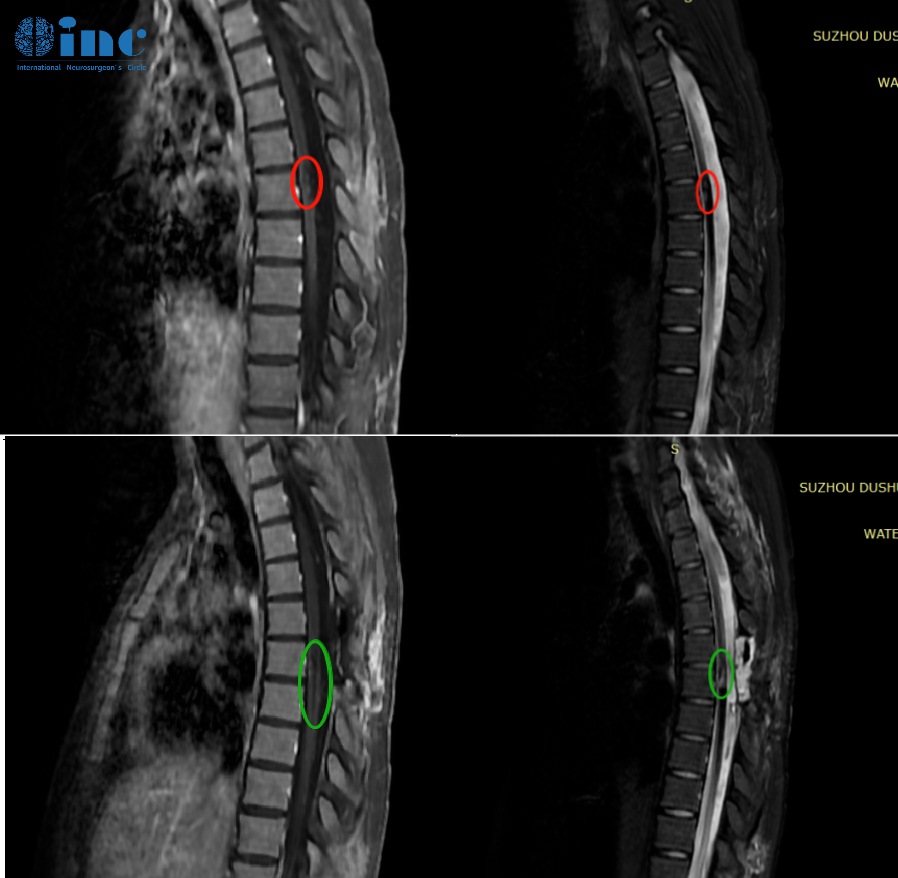

笑笑21岁,胸髓髓内海绵状血管瘤

他们为我找到了巴教授,教授对我们说,他的脊髓海绵状血管瘤手术并发症的发生率很低。这次手术的主要目标就是切除残留的血管畸形,以免将来的再次出血,我的行走问题可能在几周或几个月内有所改善,但也坦言可能无法完全恢复。

手术顺利,术后的我没有新发神经功能损伤。术后第一天,我在ICU醒来,意识清醒,能与巴教授正常交流。尽管此时我感觉右腿伸直略微困难,但术后第五天右腿活动就已经正常了,双腿肌力也十分正常。

术后两周,我已经可以下床行走,术前的症状也有所缓解。术后两个月时,我正在父母的陪伴下稳定进行康复训练。回头看,我能有现在的结果,全家人都万分感激,而我也在期待着自己未完待续的大学生活……

案例来源:2023年3月24日,巴教授在苏州大学附属第四医院手术一则。